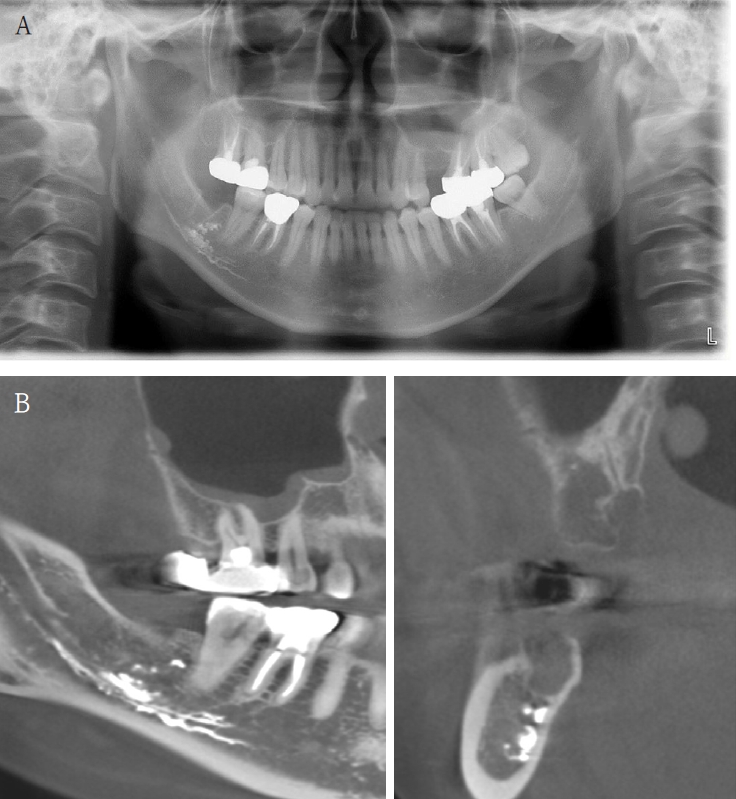

A 61-year-old female presented with intermittent right mandibular swelling and pain after root canal therapy was done using EndoSeal MTA 5 months ago. A panoramic radiograph, CBCT and bone scan confirmed material extrusion and mild localized bone changes (Fig. 4). Initial neurologic evaluation demonstrated nearly normal sensory function, with Visual Analog Scale (VAS) 4 discomfort. Surgical curettage was performed under local anesthesia. A post-operative panoramic radiograph confirmed the substantial removal of the foreign body (Fig. 5). Postoperatively, the patient reported significant improvement at both the one- and two-month follow-ups. Due to full symptom resolution, no follow-up neurosensory testing was performed.

Figure 4.

A. Pre-op panoramic radiograph of Case 3 patient. B. Pre-op CBCT of Case 3 patient. C. Pre-op bone scan of Case 3 patient